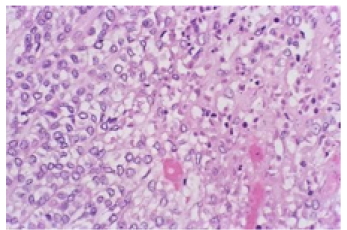

The Diminutive Seepage-Micro-secretory Adenocarcinoma

Anubha Bajaj. 22(7): 113-117.